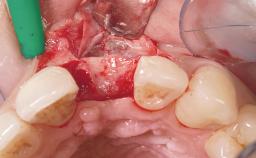

Immediate Placement of an Implant in a Maxillary Left Central Incisor Site

A 33-year-old female patient presented with an upper left central incisor that required extraction after a failed endodontic therapy. The tooth had been traumatized when the patient was a teenager and had undergone several endodontic treatments, including two apicectomy procedures. The patient was in good health and did not smoke. Clinical examination showed that the patient had a high lip line. In full smile, the gingival margins of the upper teeth were visible to the first molars. The gingival margins of central incisors 11 and 21 were only just showing. Examination of tooth 21 confirmed that the tooth was mobile and had hypererupted by 1 mm.

Soft Tissue Grafting Simultaneous

Socket Integrity Damage to one or more bone walls

Bone Volume Damage to one or more socket walls